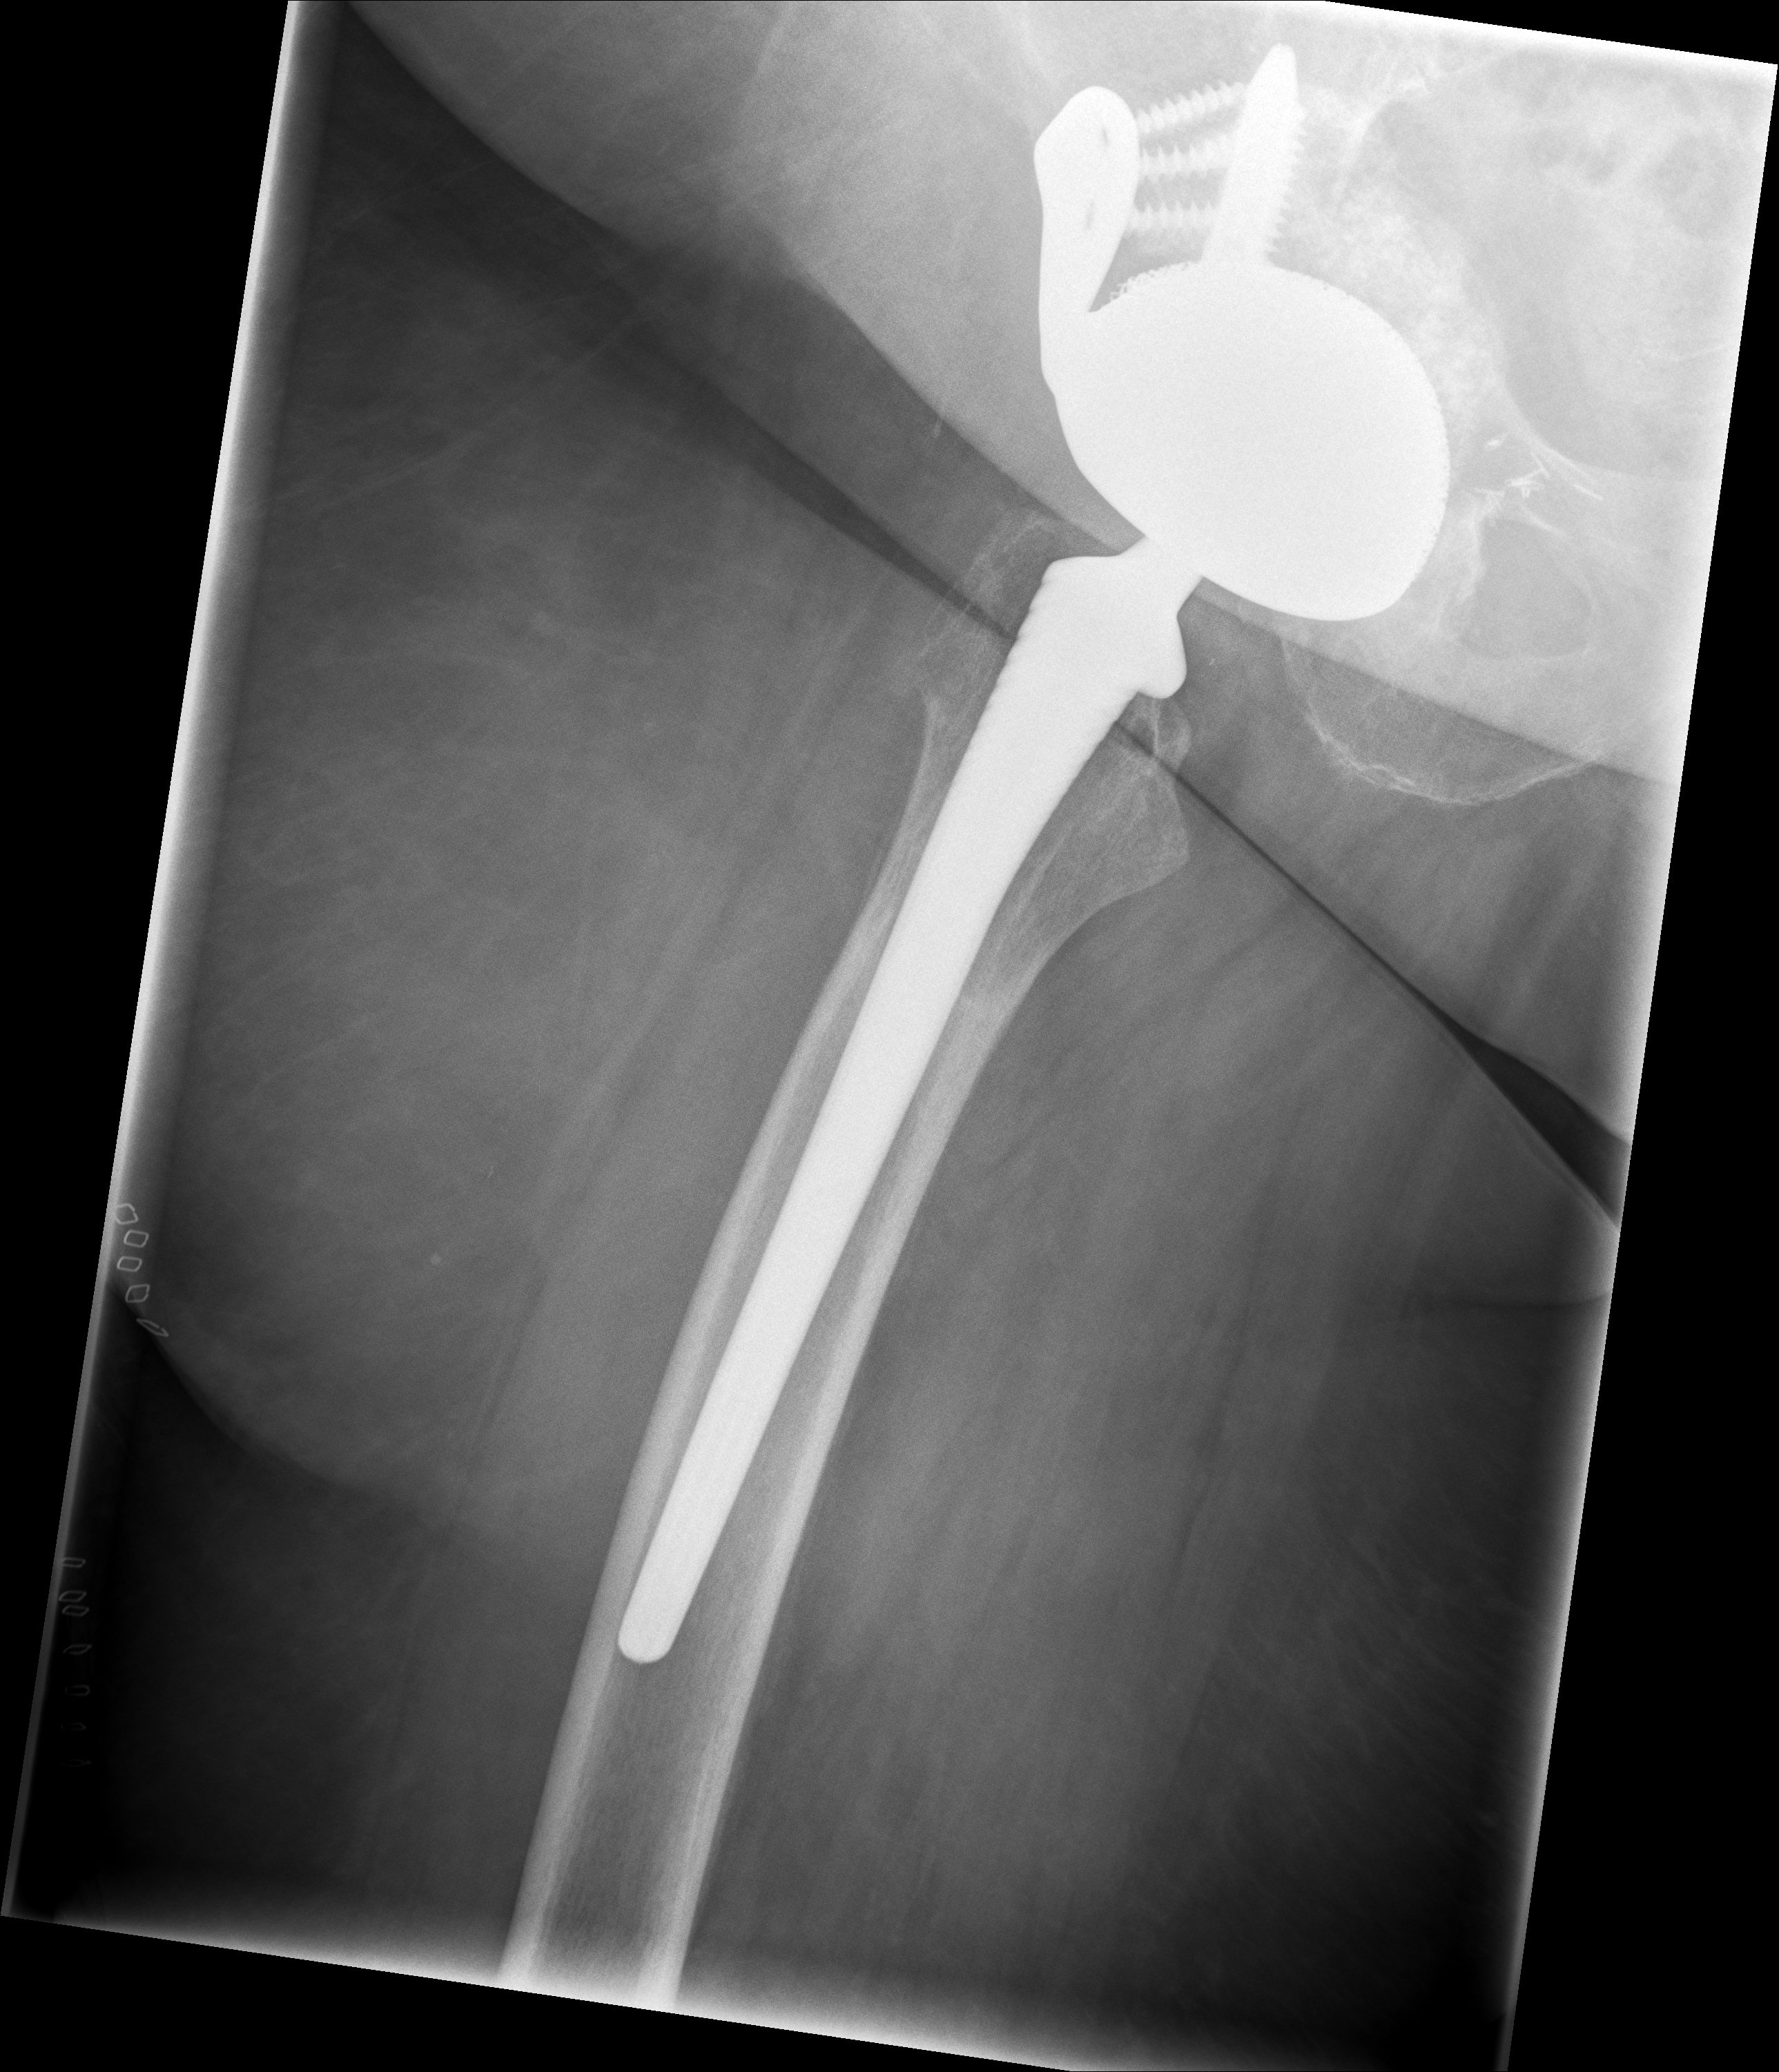

24.02.2026 - Neue TEP

Röntgen Februar 2026

Neue Hüft-TEP rechts nach Wiedereinbau

24.02.2026 - Neue TEP!

Becken 2026

Verlauf: Die Luxation/Pfannendislokation führte zur stationären Aufnahme im Universitätsklinikum Heidelberg (28.12.2025). Am 30.12.2025 wurde die TEP entfernt und ein Spacer implantiert. Infektnachweis: Enterococcus faecalis. Am 19.02.2026 wurde die neue Prothese erfolgreich eingebaut (stationär bis 05.03.2026). Komplikationsloser Verlauf, regelrechte Implantatlage im Röntgen. Entlassung mit 20kg Teillast, Amoxicillin für 6 Wochen. Wiedervorstellung am 09.04.2026.

24.02.2026 - Postoperativ

Röntgen Becken + Hüfte rechts (Kontrolle nach Wiedereinbau)

3 Aufnahmen | Becken tief + 2x Hüfte Lauenstein | 5 Tage nach OP

24. Februar 2026

Postoperative Röntgenkontrolle

Röntgen Becken tief + 2x Hüfte Lauenstein R – Kontrolle 5 Tage nach Wiedereinbau.

24.02.2026 - POSTOP

Röntgen Becken tief (nach Wiedereinbau)

DICOM

Kontrolle Becken 5 Tage nach Wiedereinbau TEP

Röntgen Hüfte Lauenstein R (1)

Kontrolle Hüfte 5 Tage nach Wiedereinbau TEP

Röntgen Hüfte Lauenstein R (2)